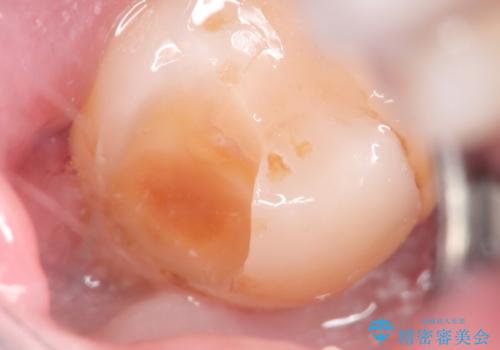

親知らずが原因の深いむし歯

- 検診にて親知らずが原因と思われる深いむし歯を発見し、親知らずを抜歯した後ゴールドインレーにて修復治療を行っております。

ゴールドインレーにて修復を行うことで適合の良い治療を行うことができました。